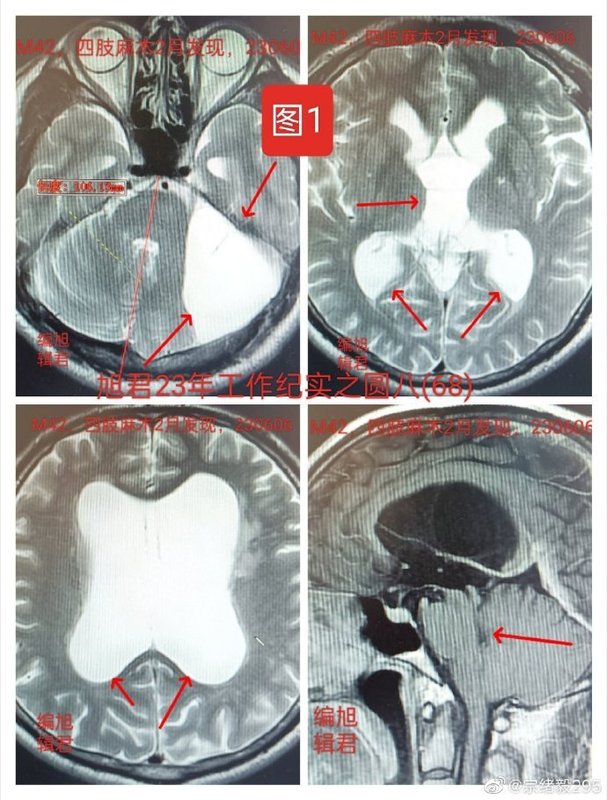

一、兩例蛛網(wǎng)膜囊腫患者的診療經(jīng)歷病例一:42歲患者的診斷和建議一位42歲的患者在兩個(gè)月前因四肢麻木、視力下降和記憶力減退進(jìn)行MR檢查,發(fā)現(xiàn)了左側(cè)頸靜脈孔區(qū)(CPA)的蛛網(wǎng)膜囊腫和梗阻性腦積水,見下【圖1-3】??紤]到手術(shù)風(fēng)險(xiǎn),建議進(jìn)行開顱切除或囊腫腹腔分流術(shù)?;颊咭蚓o張和焦慮而難以做出決定,于是來到旭君處尋求幫助。經(jīng)眼科檢查,患者視力和視野良好,無眼底水腫和視乳頭水腫。磁共振掃描顯示腦室對稱性擴(kuò)大,側(cè)腦室和三腦室內(nèi)出現(xiàn)腦脊液渦流影像,無室旁滲出,導(dǎo)水管狹窄,四腦室正常,無壓迫移位跡象。考慮到蛛網(wǎng)膜囊腫和導(dǎo)水管狹窄大多為先天性,目前沒有證據(jù)顯示顱內(nèi)壓力異常。因此,建議患者觀察6-12個(gè)月后再進(jìn)行復(fù)查對比。病例二:31歲患者的復(fù)發(fā)情況另一位31歲的患者,五年前因突發(fā)頭痛和嘔吐進(jìn)行CT和MR檢查,發(fā)現(xiàn)左側(cè)CPA蛛網(wǎng)膜囊腫。當(dāng)時(shí)醫(yī)生認(rèn)為癥狀與囊腫相關(guān),決定進(jìn)行開顱切除手術(shù)。術(shù)后患者癥狀好轉(zhuǎn),連續(xù)幾年復(fù)查未見變化,整體狀況良好。然而,術(shù)后五年的復(fù)查顯示囊腫復(fù)發(fā),壓迫腦干并導(dǎo)致四腦室移位,幕上腦室輕度擴(kuò)大,見下【圖4,術(shù)后四年和五年對比;圖5-6,術(shù)后五年圖】。目前患者無明顯頭痛等不適,眼底檢查未見水腫。二、手術(shù)策略的重要性蛛網(wǎng)膜囊腫的手術(shù)治療通常不可能完全切除囊腫壁,或者全切除會(huì)對腦組織、神經(jīng)和血管造成不可逆損傷。手術(shù)中不可避免的出血可能流入蛛網(wǎng)膜下腔,引起新的黏連和復(fù)發(fā),以及加劇創(chuàng)面疤痕化。因此,蛛網(wǎng)膜囊腫的手術(shù)關(guān)鍵不在于切除多少囊腫壁,而在于在腦動(dòng)脈周圍打通蛛網(wǎng)膜囊腫與蛛網(wǎng)膜下腔的通道。由于動(dòng)脈的波動(dòng)作用,這樣做可以促進(jìn)腦脊液流動(dòng),使造瘺口不易閉合。如果造瘺口不在動(dòng)脈周圍,就容易在短時(shí)間內(nèi)閉合,或因開顱手術(shù)后創(chuàng)面疤痕化和血液流入蛛網(wǎng)膜下腔而加速囊腫的復(fù)發(fā)。第二例患者的情況就是這樣的例子。在處理這種情況時(shí),如果有明顯的臨床癥狀,可以考慮進(jìn)行再次手術(shù)。三、結(jié)論對于蛛網(wǎng)膜囊腫的治療,需要綜合評(píng)估患者的癥狀和囊腫的特點(diǎn),制定合適的治療策略。在無明顯癥狀的情況下,觀察和定期復(fù)查可能是合適的選擇。對于復(fù)發(fā)或出現(xiàn)癥狀的情況,則可能需要考慮再次手術(shù)。無論哪種情況,醫(yī)生和患者都應(yīng)充分討論治療方案,以做出最佳決定。